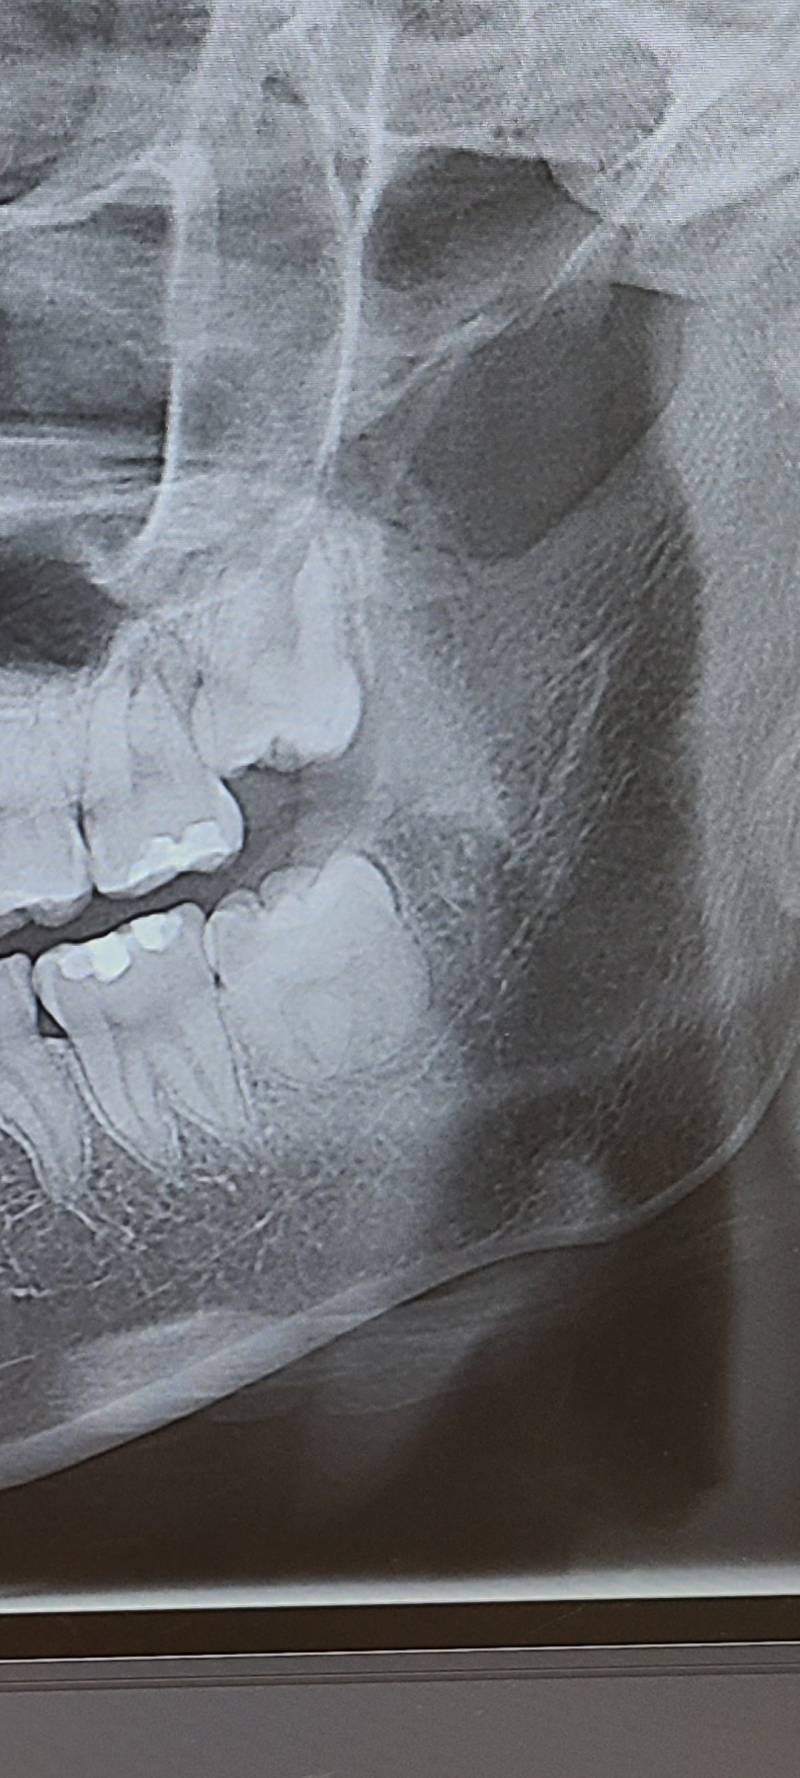

사랑니 얘네들 빼야 할까..??

빼야 할 것 같아?...

옆 치아 기대고 있어서 빼야 할듯

근데 밑에는 어금니 아니야? 밑에는 사랑니 없는것 같은뎅